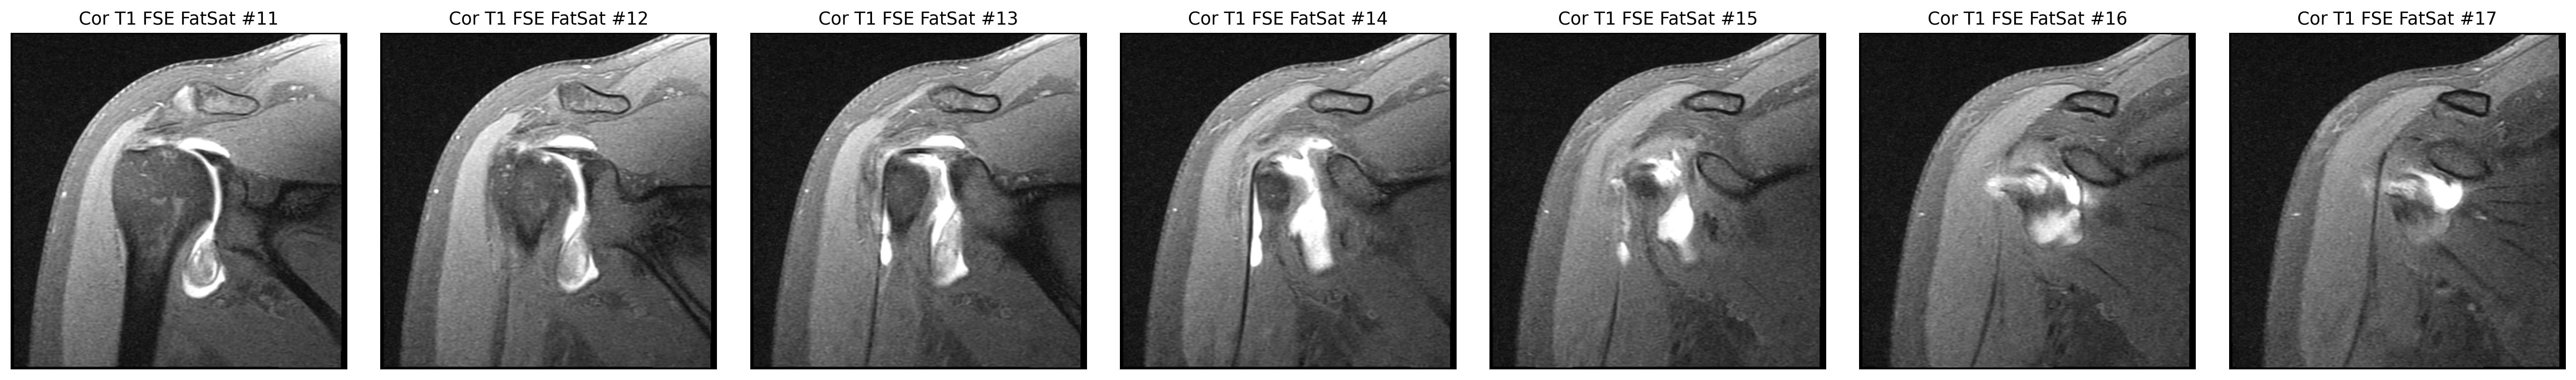

An MRI done after contrast is injected into the joint to make small internal tears easier to see.

The cuff finding was checked in coronal and sagittal views, while the labrum was reviewed on axial arthrogram slices.